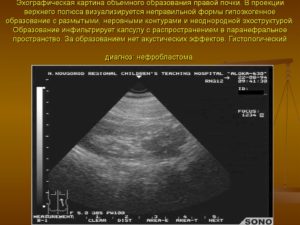

- Нефробластома – развивается преимущественно в детском возрасте. Редкий вид новообразования, встречающийся приблизительно в 8% случаев возникновения опухолей почек.